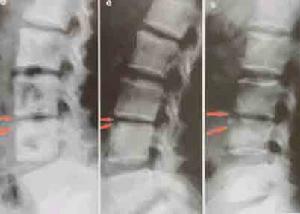

(3)、X線及CT檢查:發病2周內普通X線片可無任何異常發現,斷層攝影或CT掃描,有時可見有局限性骨質吸收或斑點狀骨質破壞。隨著病變的進展,軟骨板可出現破壞,椎體邊緣模糊呈毛刷狀。繼而椎旁軟組織腫脹,椎間隙變窄骨密度增加,骨質硬化,骨橋形成等,在早期影像學不能作出明,確診斷時應及時在CT引導下作診斷性穿刺。